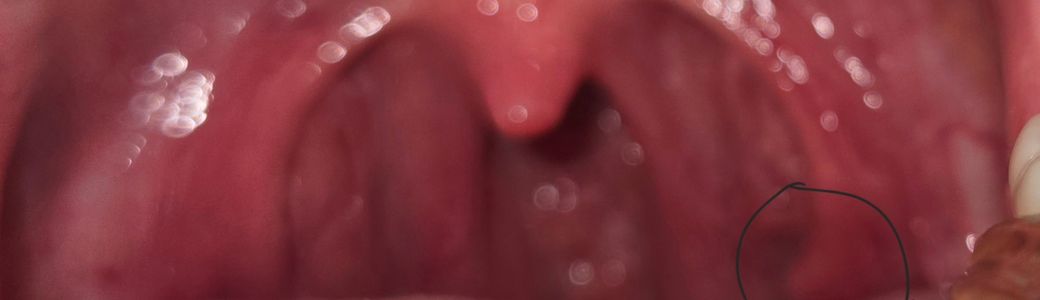

어제 오후부터 침삼키는거, 입벌리는게 힘들고 왼쪽쇄골있는안쪽 통증이 있어서 목안을 보니까 혹인지 염증같은게 있어서요...

왼쪽입니다.

올려주신 사진이 또렷하지 않아 병변을 확인하기 어렵습니다. 물을 자주 마시고 과도한 목의 사용과 음주, 흡연, 카페인, 자극적 음식의 섭취를 피하고 증상이 지속시 이비인후과 진료를 받기 바랍니다.